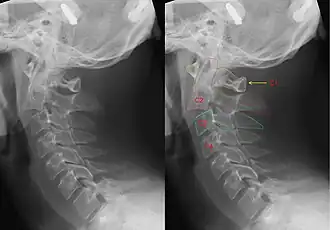

Hangman's fracture is the colloquial name given to a fracture of both pedicles, or partes interarticulares, of the axis vertebra (C2).[1]

Although a hangman's fracture is unstable, survival from this fracture is relatively common, as the fracture itself tends to expand the spinal canal at the C2 level. It is not unusual for patients to walk in for treatment and have such a fracture discovered on X-rays. Only if the force of the injury is severe enough that the vertebral body of C2 is severely subluxed from C3 does the spinal cord become crushed, usually between the vertebral body of C3 and the posterior elements of C1 and C2.